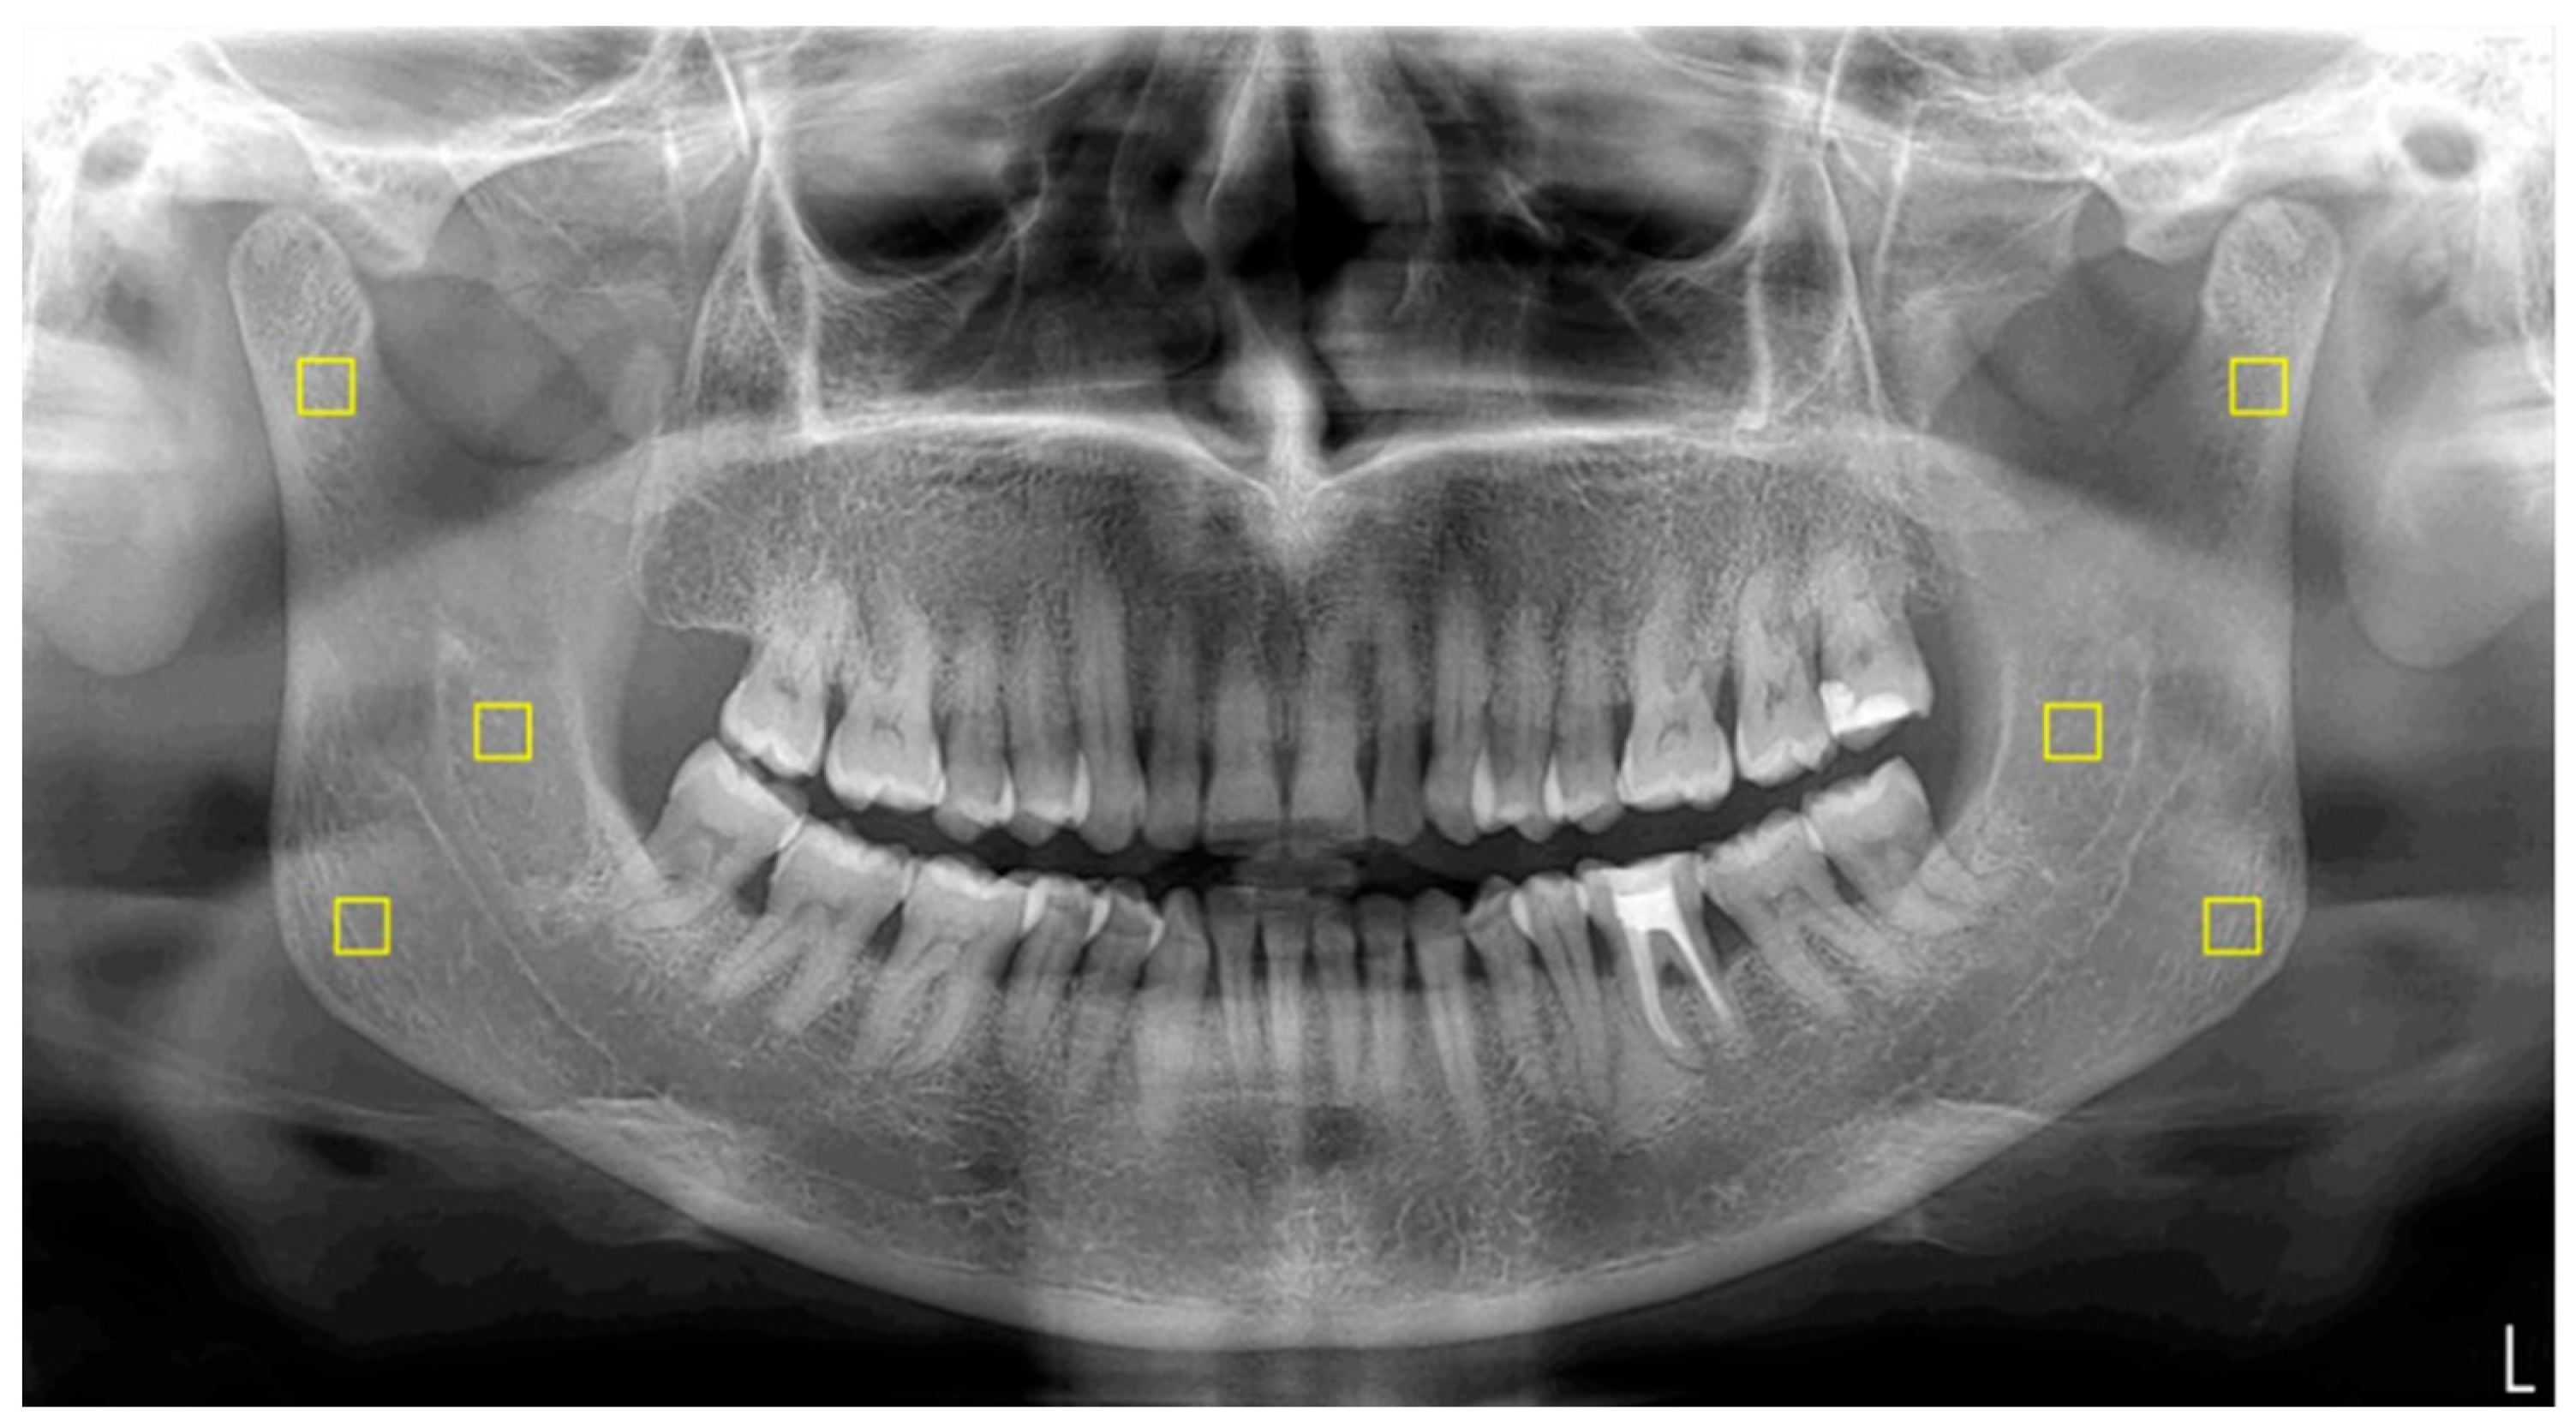

2.5. Image Processing and Fractal Analysis

The standardization of panoramic images was executed using PhotoScape X Pro 4.2.7. software (MOOII Tech, Seoul, Republic of Korea). All images were resized to 1024 × 499 pixels at a resolution of 600 dpi and saved in TIF format. FD values were determined utilizing ImageJ version 1.54 software, implementing the box-counting method introduced by White and Rudolph [

18,

19]. Regions of interest (ROIs) measuring 25 × 25 pixels were bilaterally selected from the mandibular angle, ramus, and condylar neck (

Figure 1). Each ROI was subjected to digital preparation, including rotation, magnification, cropping, and duplication. A Gaussian blur filter was applied to reduce grayscale density variations and to emphasize trabecular structures (

Figure 2). The resulting values were then plotted on a logarithmic scale to determine the slope of the line that best fit the points on the graph, which was defined as the FD (

Figure 3).